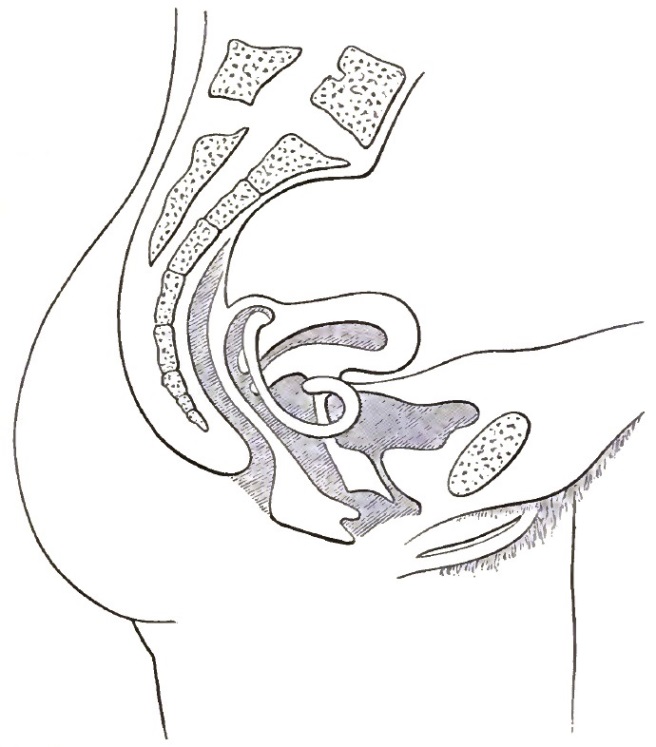

| 17. | COMPLETED REPOSITION OF THE RETROVERTED OR RETROFLEXED UTERUS BY CONJOINED MANIPULATION |